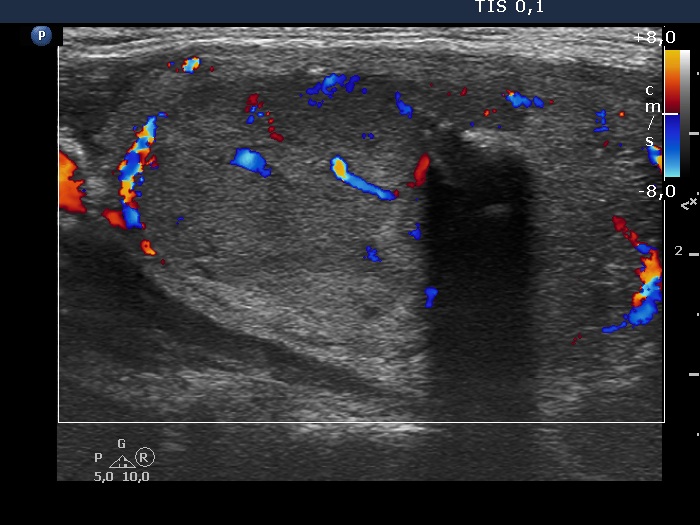

Left lobe, longitudinal view, color Doppler mode. The nodule has intranodular vascularization, too.